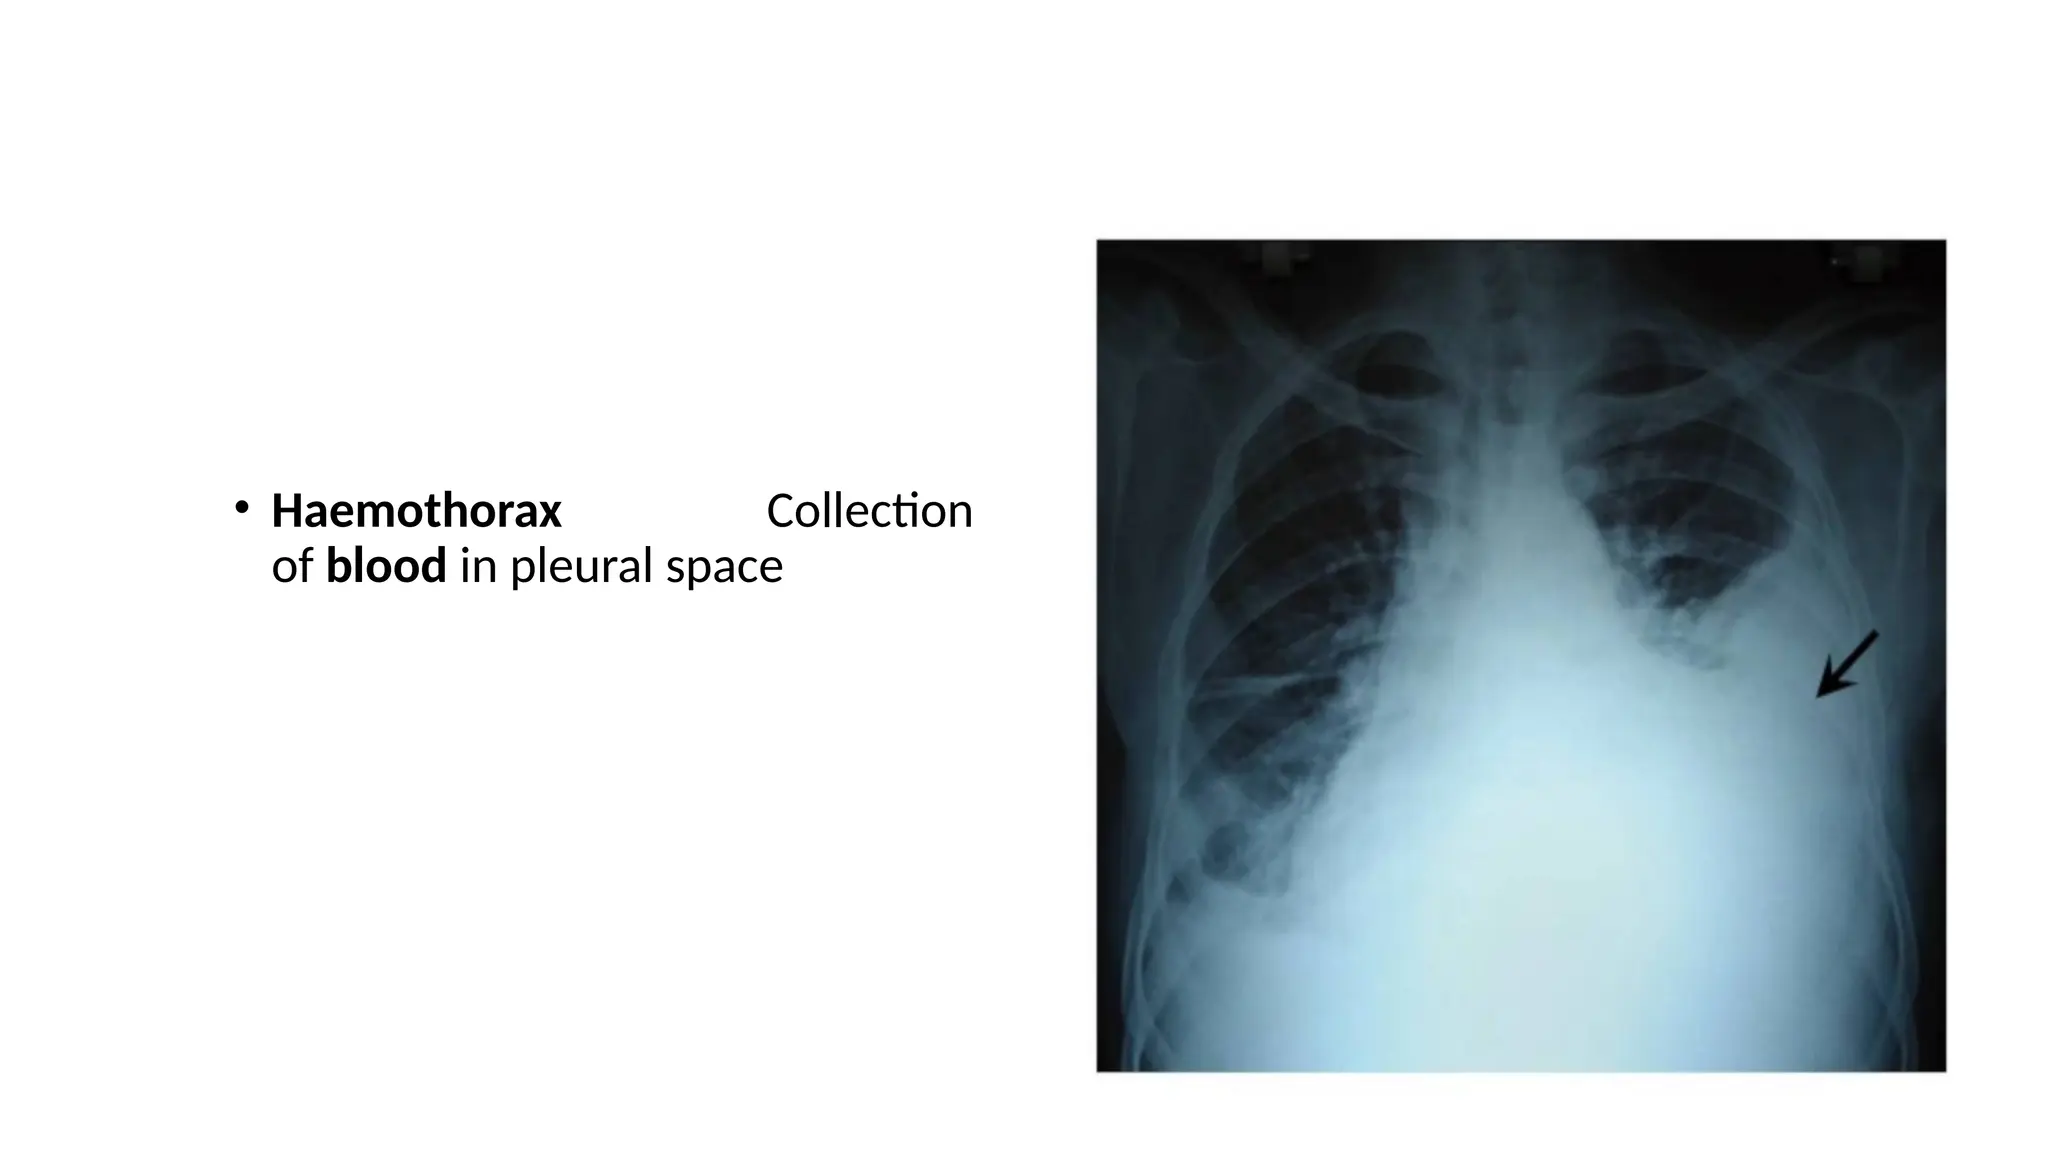

• Haemothorax Collection

of blood in pleural space

• Haemothorax Collection ofblood in pleural space

• 42.